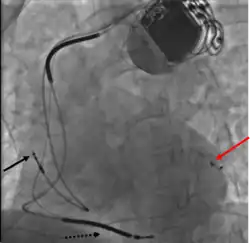

Right ventricular lead placement

A venipuncture is made, and a guide wire inserted into the vein, where it is guided, with use of real time X-ray imaging, through to the right ventricle. The guide wire is then used to assist in the placement of the electrode lead, which travels through the venous system into the right ventricle where the electrode is embedded.[1]

Left ventricular lead placement

This is generally performed subsequent to RV lead placement, with the RV lead providing a backup in case of accidental damage to the electric fibers of the heart, causing an asystolic event. As with the RV lead, a guide wire is first inserted, allowing for the insertion of a multi-delivery catheter. The catheter is subsequently maneuvered to the opening of the coronary sinus in the right atrium. From here a contrast media is injected, allowing the surgical team to obtain a coronary sinus phlebogram to direct the placement of the lead into the most suitable coronary vein.[1]

Once the phlebogram has been obtained, the multi-delivery catheter is used to guide in the lead, from the chosen vein of entry, into the right atrium, through the coronary sinus and into the relevant cardiac vein.[1]

Left ventricular lead placement is the most complicated and potentially hazardous element of the operation, due to the significant variability of coronary venous structure. Alterations in heart structure, fatty deposits, valves and natural variations all cause additional complications in the process of cannulation.[1] However, this risk can be reduced using AI-based[8] preoperative visualization of LV venous anatomy using computer tomography (CT) imaging.